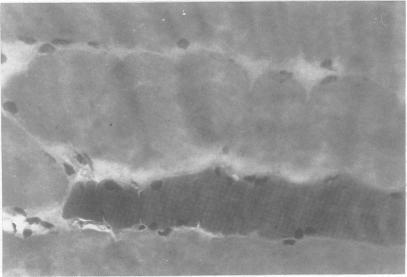

A detailed pathological description of the muscle findings in a case of the neuroleptic malignant syndrome (NMS) following ingestion of lysergic acid diethylamide (LSD) is given, including the first ultrastructural analysis. Focal necrosis, oedema, and hypercontraction of fibres with glycogen and lipid depletion, were identified, all of which had resolved completely a year later. The findings are compared with those in malignant hyperthermia. It is suggested that the results support the view that in NMS, the muscle rigidity is due to central mechanisms and, in both this disorder and malignant hyperthermia, it is responsible for the hyperpyrexia and its life-threatening complications.

本文给出了一例服用麦角酸二乙酰胺(LSD)后发生神经阻滞剂恶性综合征(NMS)患者肌肉检查结果的详细病理学描述,包括首次超微结构分析。发现有局灶性坏死、水肿以及纤维的过度收缩,并伴有糖原和脂质耗竭,所有这些在一年后已完全消退。将这些发现与恶性高热的发现进行了比较。结果表明支持以下观点:在NMS中,肌肉强直是由中枢机制引起的,并且在这种疾病和恶性高热中,它都是高热及其危及生命并发症的原因。